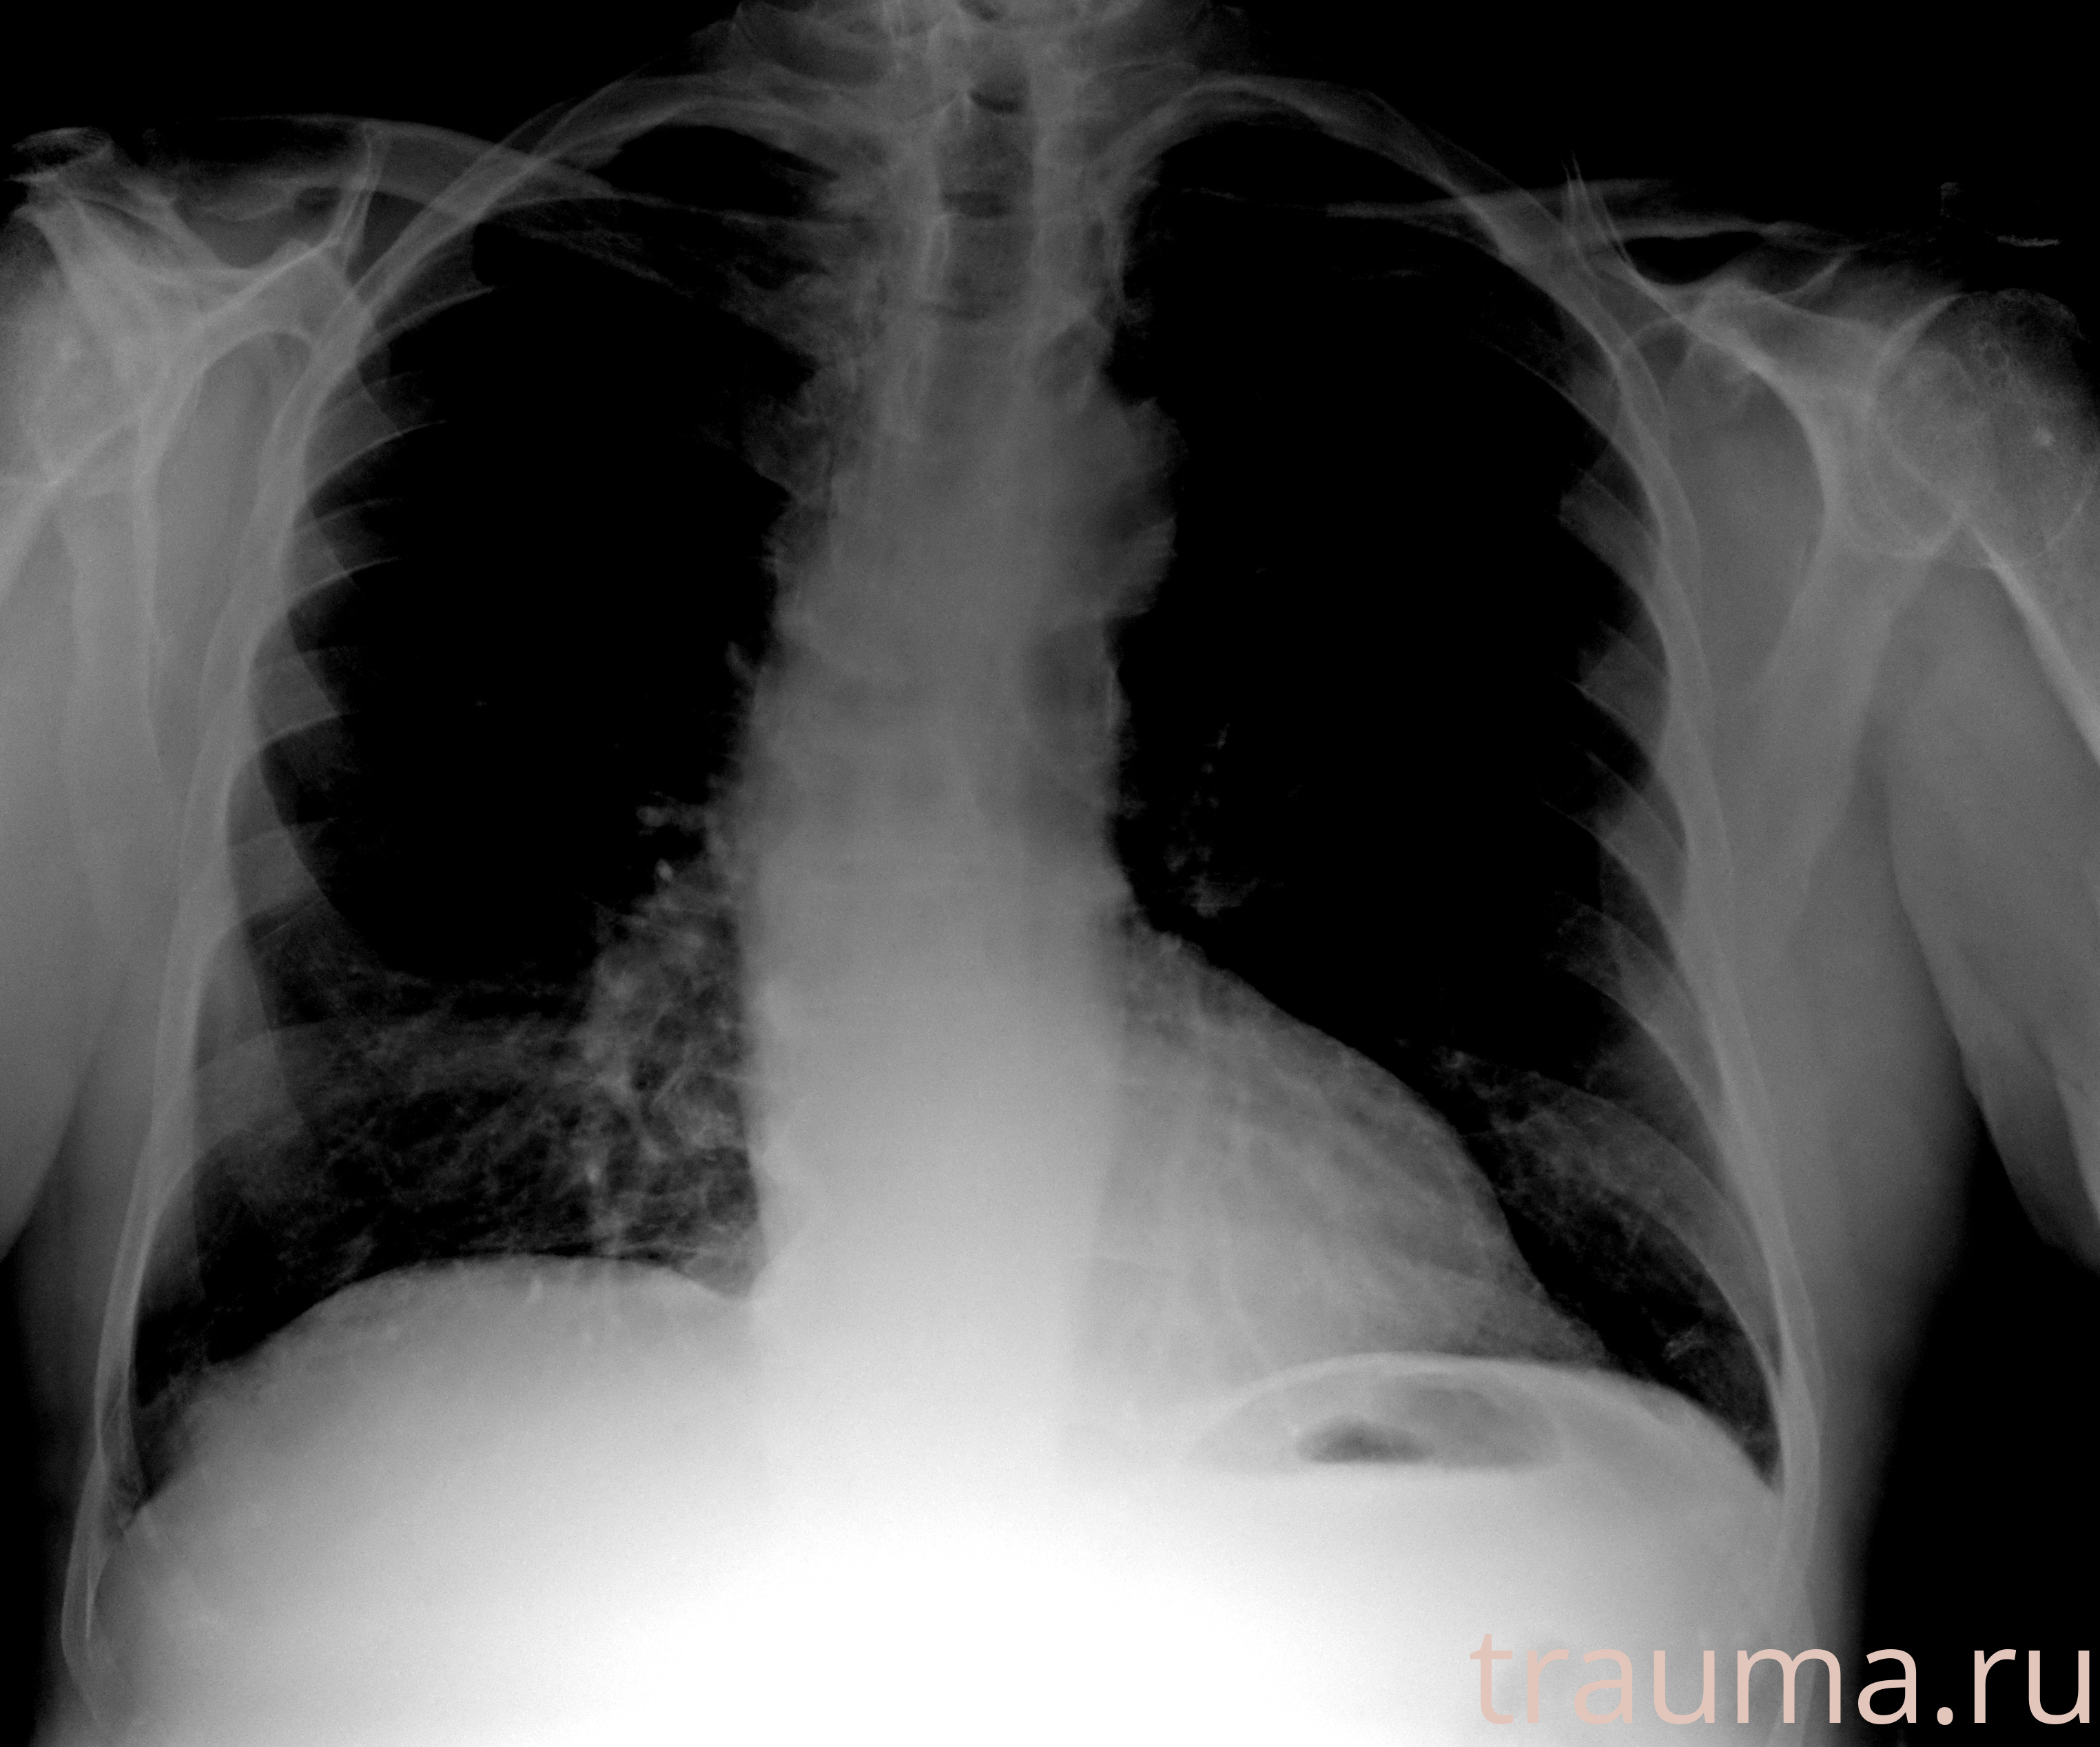

Рентгенограммы

Рентген на дому: по вашему адресу приезжает врач-рентгенолог, травматолог-ортопед с мобильным рентгеновским аппаратом, проводит диагностику травмы или заболевания, делает необходимые рентгенограммы, дает рекомендации по дальнейшему лечению. Получить качественные снимки в домашних условиях возможно благодаря уникальной методике, разработанной МосРентген Центром для института  Склифосовского

при переломе шейки бедра и пневмонии от компании МосРентген Центр - партнера Института имени Склифосовского